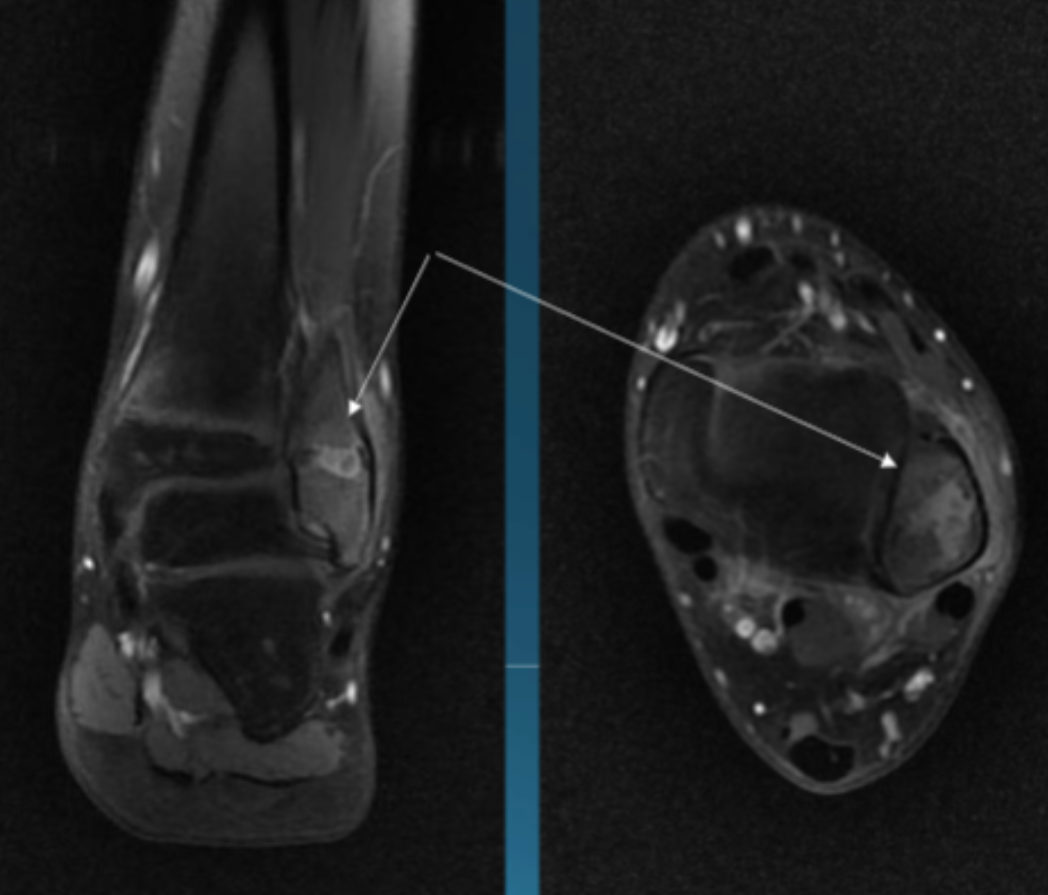

Describe the pathology indicated by the arrow (Cor T1 FS +C).

Osteomyelitis (focal)